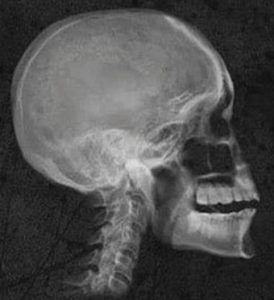

X-rays

![]() |

X-rays, or radiography, use ionizing radiation to produce images of the body's internal structures | -Digital Imaging Systems

-Analog Imaging Systems |

– General radiology

– Dental - Fluoroscopy – Mammography |